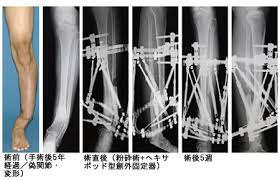

難治骨折診 帝京大学医学部 整形外科学講座